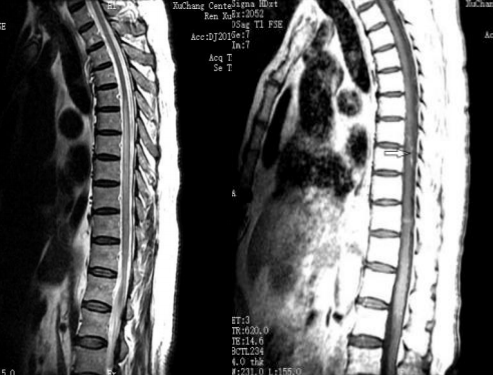

病例11

患者女性,26岁,“反复四肢抽搐 11年,言语不利、反应迟钝4天”入院。患者15岁时首次出现癫痫样发作,表现为口吐白沫,头向右侧歪斜,四肢抽搐,伴有意识丧失,持续数秒钟后自行缓解,间隔一段时候后再发,每次发作前多有发热,头痛诱因,诊断为“癫痫”,予德巴金治疗,自行服用半年后停用。患者分别在19岁,21岁,25岁以及今年11月份出现上述癫痫样发作,患者家属诉患者每次癫 痫发作时持续时间均不足1分钟,发作频繁,间歇期逐渐缩短。患者4天前出现言语不利、反应迟钝。

2018.11.3核磁如下:

2018.12.27核磁如下:

2019.1.19核磁如下:

答案:MELAS。其影像典型表现:CT:部分见基底节钙化。MRI:T2WI,FLAIR,DWI序列上相应的高信号;ADC可为高信号,低信号或混杂信号,提示细胞毒性水肿和血管源 性水肿同时存在;磁共振波谱(MRS)提示脑部乳酸的存在。病灶多分布在皮层和皮层下白质,深部皮层不受累;急性到亚急性时期病灶变化可有明显波动,迁移至完全消失;反复发作后脑萎缩。